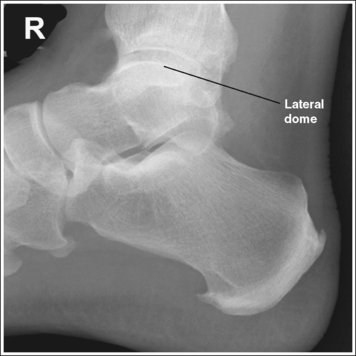

The ankle is in a lateral projection. The domes of the talus are superimposed, the tibiotalar joint is open, and the distal fibula is superimposed by the posterior half of the distal tibia.

• To obtain a lateral ankle projection, begin with the patient in a supine position, with the leg extended (Figure 6-57) and the foot dorsiflexed until its long axis forms a 90-degree angle with the lower leg. Rotate the patient and affected leg until the lateral foot surface is against the IR, and then adjust the degree of rotation until the surface is aligned parallel with the IR (Figure 6-58). For most patients, this positioning places the lower leg parallel with the imaging table. If this is not the case, as with a patient with a large upper thigh, the foot and IR should be elevated until the lower leg is parallel with the imaging table.

• Effect of lower leg positioning on talar dome superimposition. Often, if the knee is not fully extended (Figure 6-59) or if the distal tibia is not elevated to place the lower leg parallel with the IR in a patient with large upper thighs, the proximal tibia is positioned farther from the imaging table than the distal tibia. The resulting image demonstrates the lateral talar dome proximal to the medial talar dome and the height of the longitudinal arch appears less than it actually is because the cuboid shifts anteriorly and the navicular bone moves posteriorly in this position and the talocalcaneal joint will be narrowed (see Image 43). If the distal tibia is positioned farther from the table than the proximal tibia, the medial talar dome is demonstrated proximal to the lateral dome, and the height of the longitudinal arch appears greater than it actually is because the cuboid shifts posteriorly and the navicular bone moves anteriorly in this position and the talocalcaneal joint will be widened (see Image 44). When viewing a lateral ankle projection that demonstrates one of the talar domes proximal to the other, evaluate the height of the longitudinal arch and the degree of talocalcaneal joint visualization to determine which dome is the proximal dome. If the navicular bone is superimposed over more of the cuboid than expected and a narrowed talocalcaneal joint is seen, the lateral dome is the proximal dome. If the navicular bone is superimposed over less of the cuboid than expected and a wider talocalcaneal joint is seen, the medial dome is the proximal dome.

• Effect of foot positioning on talar dome superimposition. To demonstrate accurate AP alignment of the talar domes, position the lateral surface of the foot parallel with the IR. If this surface is not parallel with the IR, the talar domes are demonstrated one anterior to the other. When the leg is rotated more than needed to place the lateral foot surface parallel with the IR (leg externally rotated), as shown in Figure 6-60, the medial talar dome is demonstrated anterior to the lateral talar dome (see Image 45). If the leg is not rotated enough to place the lateral foot surface parallel with the IR (leg internally rotated), as shown in Figure 6-61, the medial talar dome is demonstrated posterior to the lateral talar dome (see Image 46). When taking a lateral ankle projection that demonstrates one of the talar domes anterior to the other, observe the position of the fibula in relation to the tibia to determine how the patient should be repositioned. On most lateral ankle projections with accurate positioning, the fibula is positioned in the posterior half of the tibia. On a lateral projection with poor positioning, if the fibula is demonstrated more posteriorly, the medial dome is anterior and the patient was positioned with the forefoot depressed and the heel elevated (leg externally rotated), as shown in Figure 6-60. If the fibula is demonstrated more anteriorly, the medial domes are posterior and the patient was positioned with the forefoot elevated and the heel depressed (leg internally rotated), as shown in Figure 6-61.

The long axis of the foot is positioned at a 90-degree angle with the lower leg.

• In most cases, when the patient is relaxed, the foot rests in plantar flexion. Plantar flexion results in a forced flattening of the anterior pretalar fat pad, reducing its usefulness in the detection of joint effusion (see Image 47). Consequently, it is best to dorsiflex the patient's foot, placing its long axis at a 90-degree angle with the lower leg. This positioning also places the tibiotalar joint in a neutral position and helps prevent the leg from rolling too far anteriorly. Anterior foot rotation elevates the heel and rotates the foot.